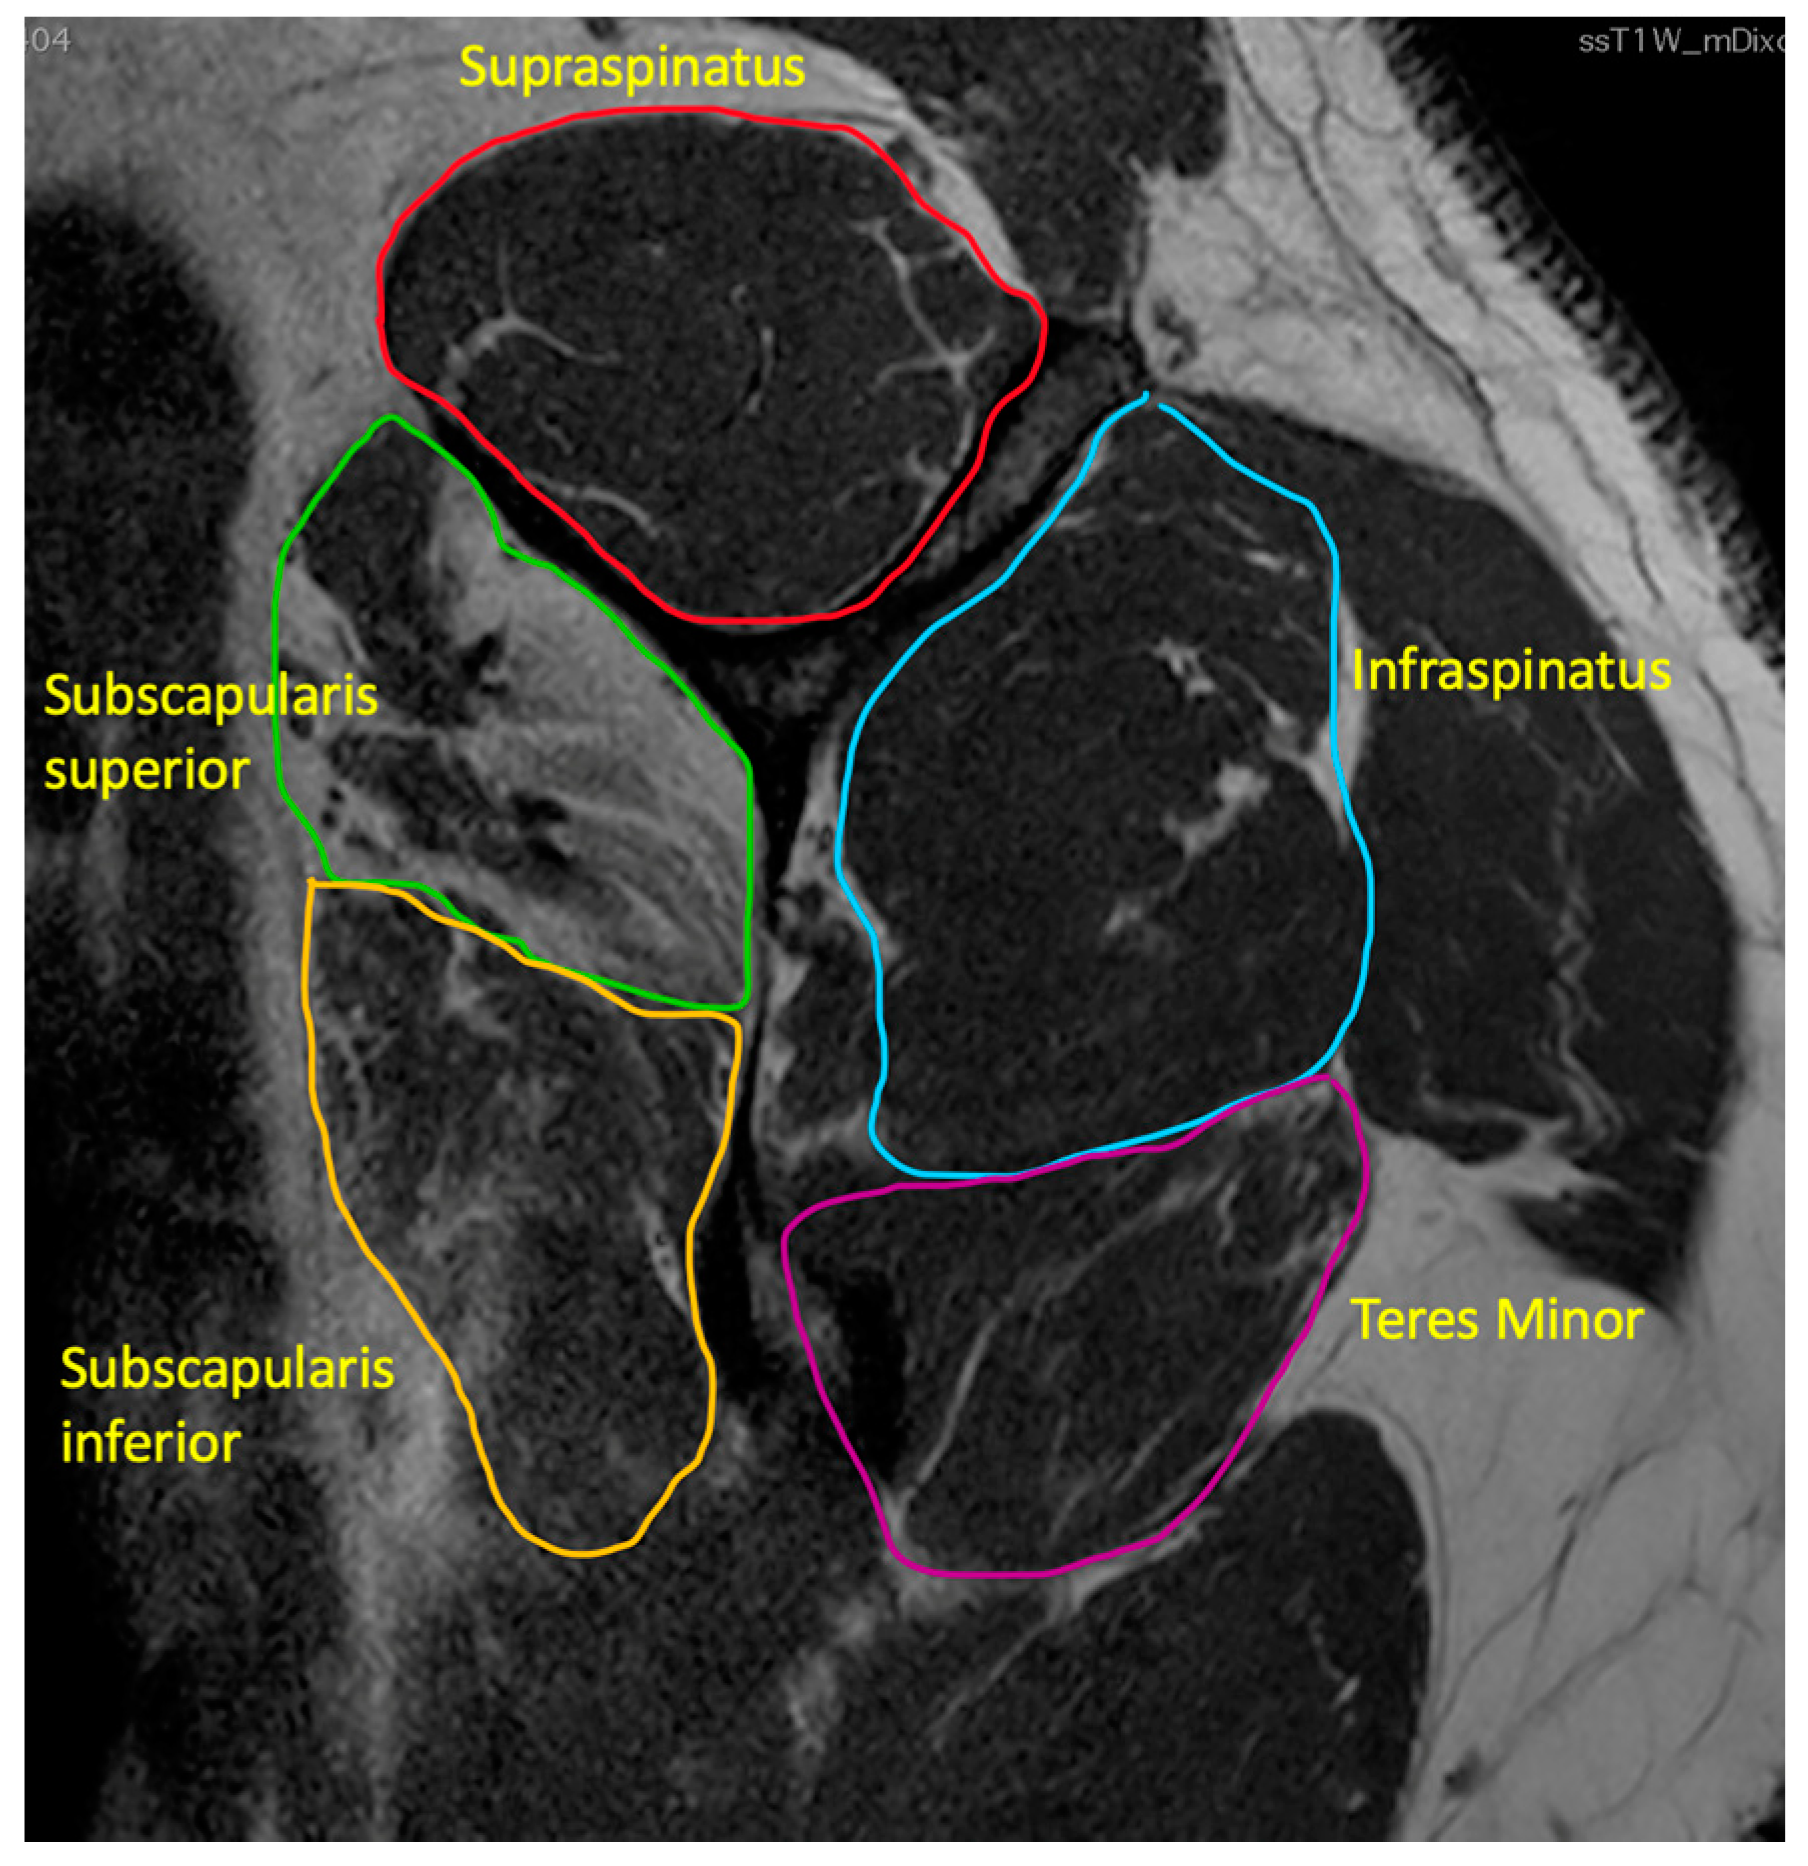

- Fatty infiltration

- 3.